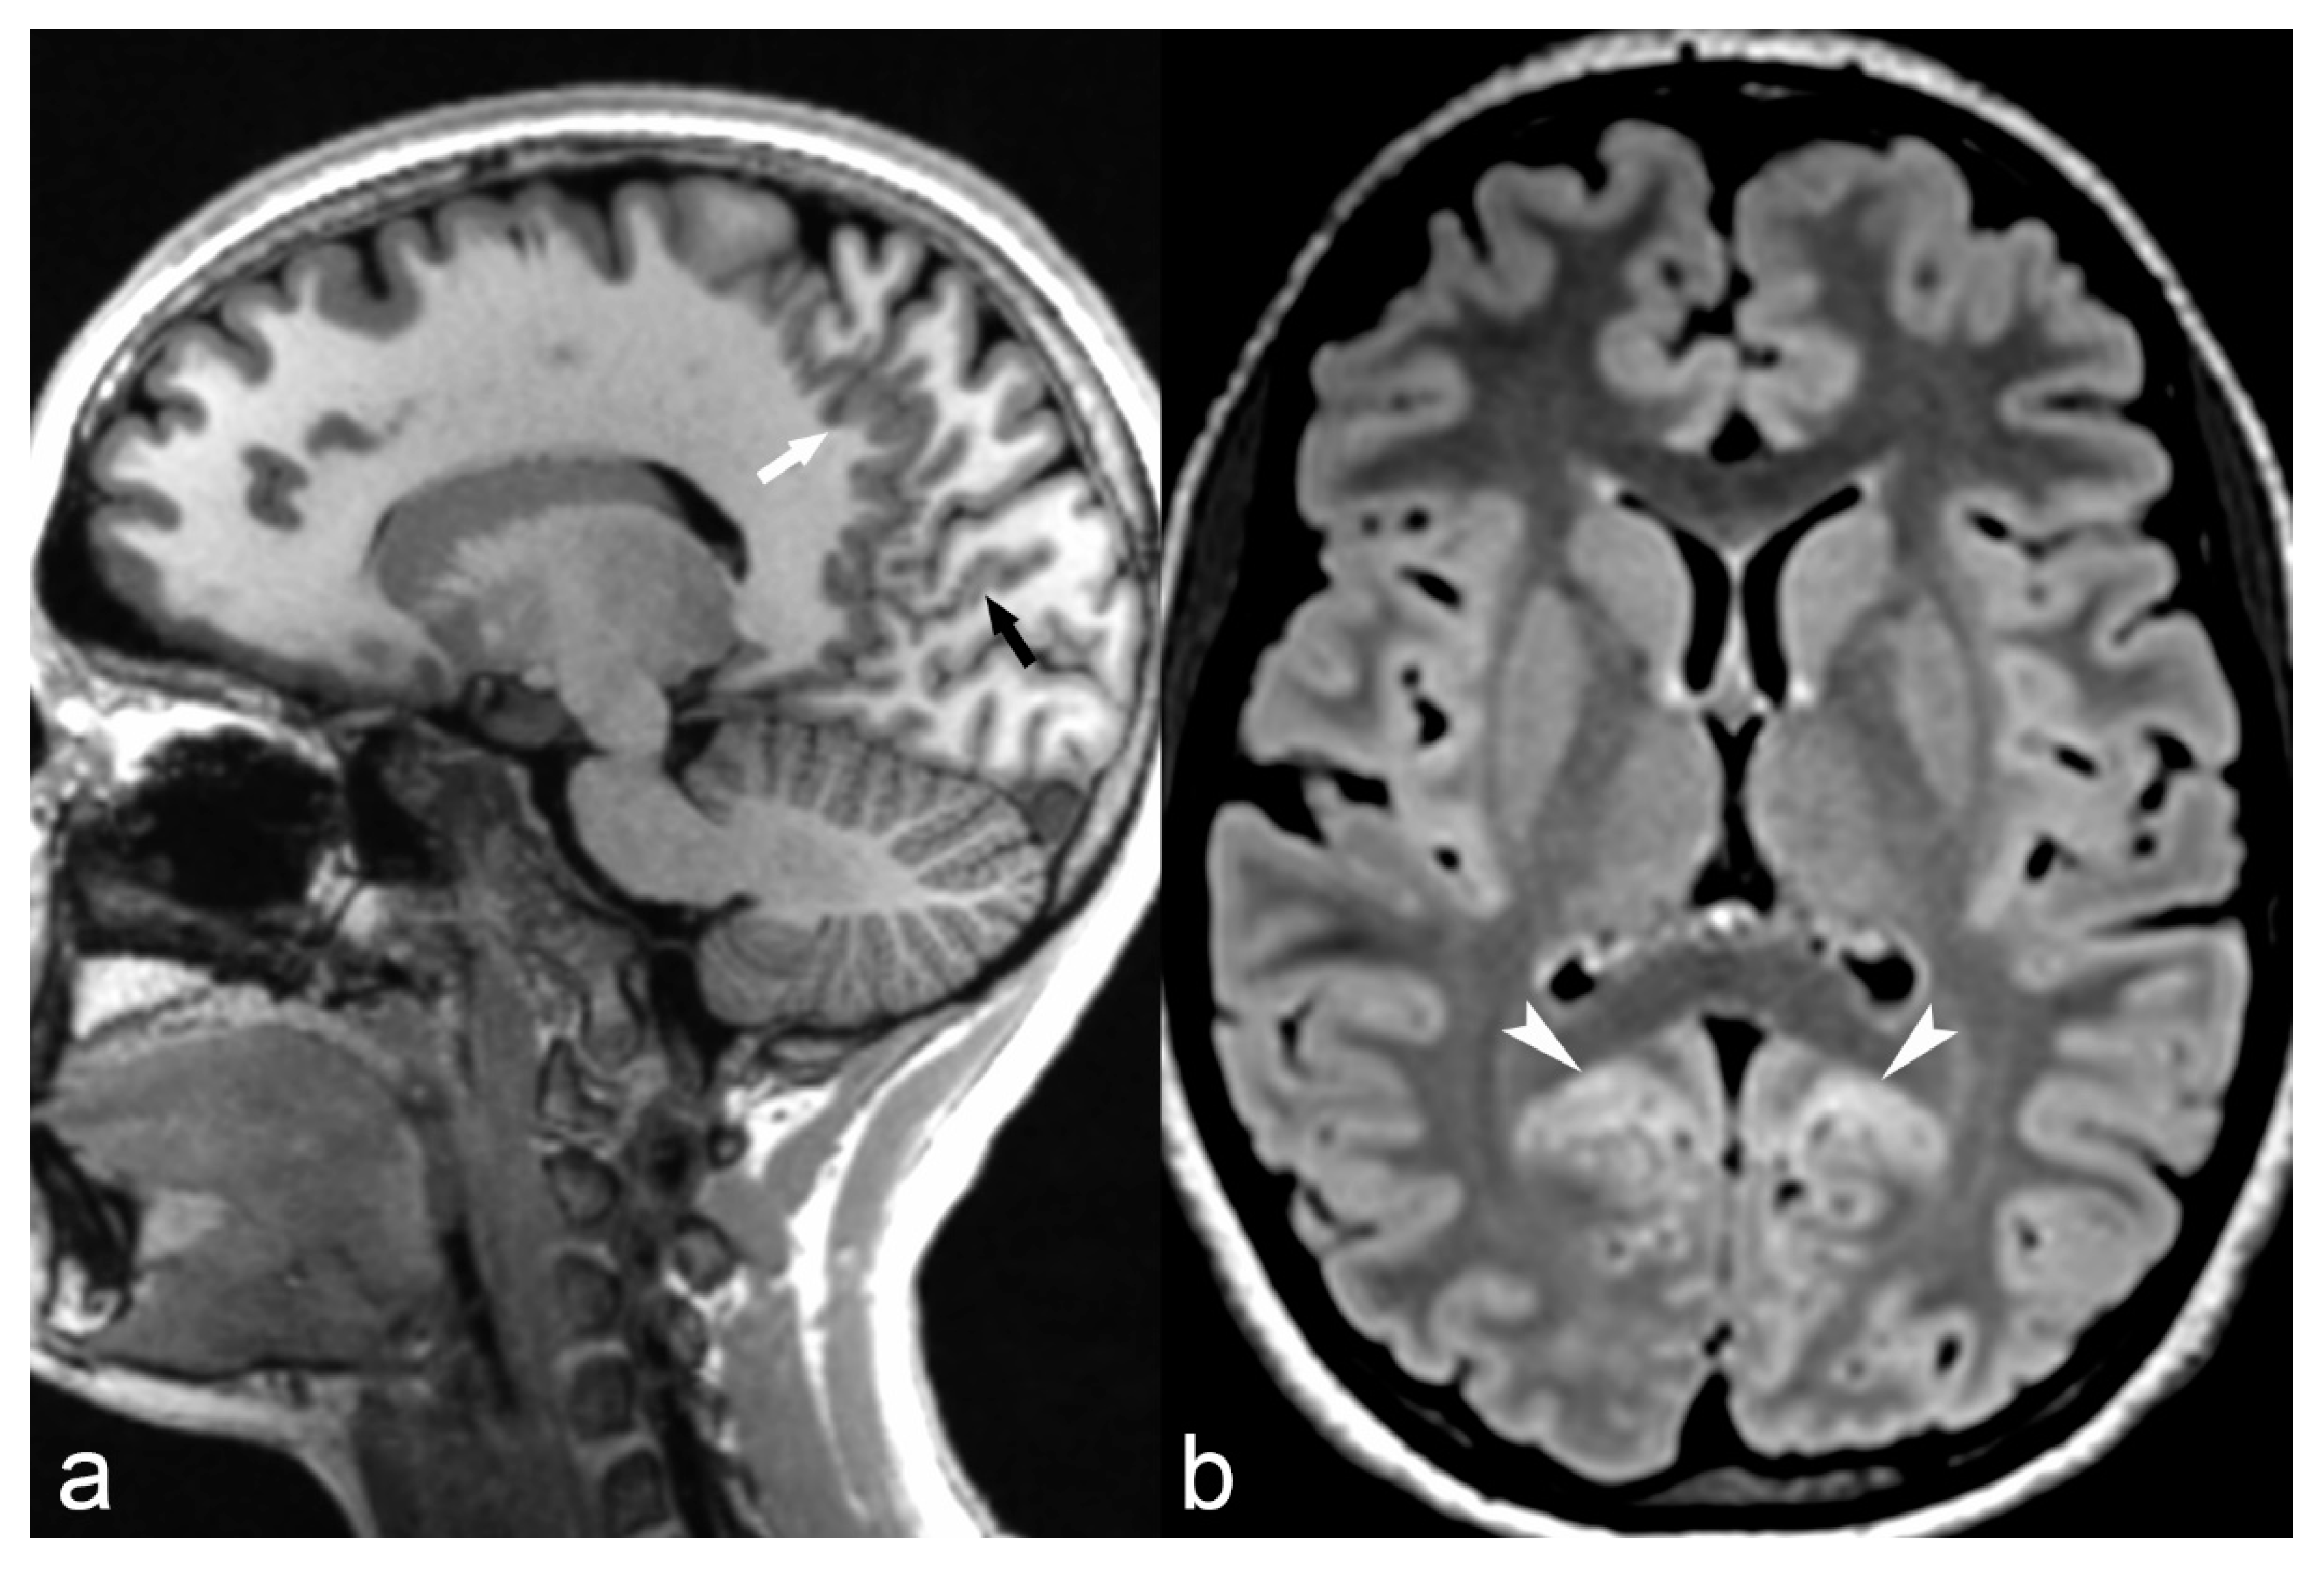

The magnetization-prepared two rapid acquisition gradient echoes (MP2RAGE) sequence is a volumetric T1 weighted novel sequence, which acquires two gradient echo images after an inversion pulse and is currently used as part of the routine epilepsy protocol in our institution. It provides excellent contrast-to-noise ratio with minimal effect of B1 inhomogeneity (B1 is the radiofrequency field, which is applied perpendicular to the main magnetic field of an MRI machine) and improved delineation of gray/white matter interface (well demonstrated in Figure 2a) and has, therefore, allowed increased detection and characterization of subtle cortical malformations, especially FCD [33]. Furthermore, it allows automated volume calculation of different brain regions [33].

Figure 2.

14-year-old female with parieto-occipital polymicrogyria. Sagittal T1 magnetization/prepared-2-rapid-acquisition-gradient-echo (MP2RAGE) (a) image showing numerous small gyri involving the parasagittal parieto-occipital region (arrow) and calcarine sulcus (black arrow) with mild cortical hyperintensity (arrowheads) on axial FLAIR (b) images suggestive of polymicrogyria.